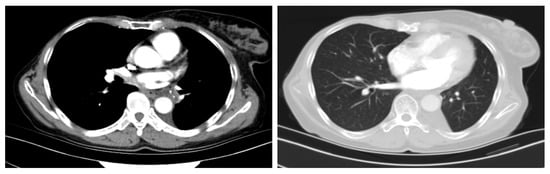

2. Case Presentation